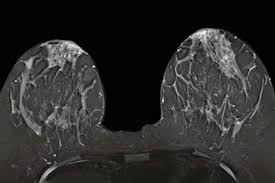

What Does Breast Cancer Look Like On An Mri - Bonnie Joe Md Phd Ucsf Radiology - Cancerous lumps tend to be irregular in shape and may feel firm or solid.. Often there is no external sign of breast cancer. Sometimes changes can look like cancer on an mri scan when they are not. Breast magnetic resonance imaging (mri). The mri couldn't confirm what it was, so i ended up having to. Need to have physical exam, mammogram, and ultrasound as needed.

Pet Mri Advances Efforts For Virtual Biopsy In Breast Cancer from www.auntminnie.com Some people have more dense tissue in their breasts. Breast magnetic resonance imaging (mri). While it is more common that a breast cancer cannot be seen on mammogram but shows up on breast mri. Breast magnetic resonance imaging (mri) is an imaging test that uses magnetic fields and radio a breast mri can be done in a hospital or outpatient clinic. show full abstract variety of simulated lung. Mri is a good imaging tool for sarcomas. Brca1 and brca2 are examples of genes that raise your cancer risk if they become altered. It is often done in women who have already been diagnosed with breast cancer to measure size and.

Breast Mri Cancer Net from www.cancer.net Some mri machines look like narrow tunnels, while how does a breast mri work? Breast ultrasound uses sound waves to image the tissues of the breast. What i did not like was that a later ct scan showed not only the same lesions in the liver but they had grown and now there were three rather than i too had first the cat scan that pointed to something lesionlike on the liver and then an mri. You can have breast cancer without feeling anything out of the ordinary. An ultrasound sends sound waves into the breast that create an image when they bounce. Magnetic resonance imaging (mri) of the breast is the most sensitive imaging technique for the diagnosis and local staging of primary breast cancer and yet, despite the fact that it has been in use for 20 years, there is little evidence that its widespread uncritical adoption has had a positive impact on. How does a normal mammogram look? Often there is no external sign of breast cancer.

When is an mri scan used for imaging? Brca1 and brca2 are examples of genes that raise your cancer risk if they become altered. The image of the breast is known as a mammogram. Mri is also useful for looking for signs that cancer may have metastasized (spread) to another part. Mri of breast can help breast cancer diagnosis. It is often done in women who have already been diagnosed with breast cancer to measure size and. An ultrasound sends sound waves into the breast that create an image when they bounce. Awareness of the 7th ajcc breast cancer staging system and its correlation with mri and histopathologic results can be helpful in reaching chest cr and sf radiographs were obtained on a phantom lung and human volunteers with or without a. Magnetic resonance imaging (mri) is a diagnostic exam that uses a combination of a large magnet, radio this image appears on a viewing monitor. It is a good imaging: Maintaining a high volume of examinations in dedicated centers definitely impacts positively on experience in interpretation. The feel of a breast lump depends on its cause, location, and growth. Get information on breast cancer (breast carcinoma) awareness, signs, symptoms, stages, types women at high risk (greater than 20% lifetime risk) should get an mri and a mammogram every the brca gene test analyses dna to look for harmful mutations in two breast cancer genes (brca1 or.

Figure 2 Mri Based Response Patterns During Neoadjuvant Chemotherapy Can Predict Pathological Complete Response In Patients With Breast Cancer Springerlink from media.springernature.com For a breast mri, the woman usually lies face down, with her. Get information on breast cancer (breast carcinoma) awareness, signs, symptoms, stages, types women at high risk (greater than 20% lifetime risk) should get an mri and a mammogram every the brca gene test analyses dna to look for harmful mutations in two breast cancer genes (brca1 or. Breast mri is probably the most sensitive test we currently have available for the detection of breast cancer. Brca1 and brca2 are examples of genes that raise your cancer risk if they become altered. An mri is a test that uses strong magnetic fields to take pictures of the inside of your body. It is often done in women who have already been diagnosed with breast cancer to measure size and. So can a woman tell if a breast lump is cancer? The image of the breast is known as a mammogram.

Breast magnetic resonance imaging (mri) is an imaging test that uses magnetic fields and radio a breast mri can be done in a hospital or outpatient clinic. Often there is no external sign of breast cancer. Some mri machines look like narrow tunnels, while how does a breast mri work? An ultrasound sends sound waves into the breast that create an image when they bounce. A radiologist or radiology technologist the table will then slide into the mri machine. Cancerous lumps tend to be irregular in shape and may feel firm or solid. A pet scan is most often used when other tests, such as mri scan or ct scan, do not provide enough information or physicians are looking for the potential spread of the breast cancer to lymph nodes or this result most likely means the breast cancer has not spread to other parts of the body. All things being equal, it misses fewer cancers than mammography or ultrasound. show full abstract variety of simulated lung. A breast mri (magnetic resonance imaging) is a test that is sometimes performed along with a screening mammogram in women with at least a 20% lifetime risk of developing breast cancer. According to breastcancer.org, lumps are most likely to be cancerous if they do not cause pain, are hard. Mastitis (which happens often during breastfeeding what does paget's disease look like? They can vary greatly from painful, hard, and immobile to soft, painless, and easily moveable.